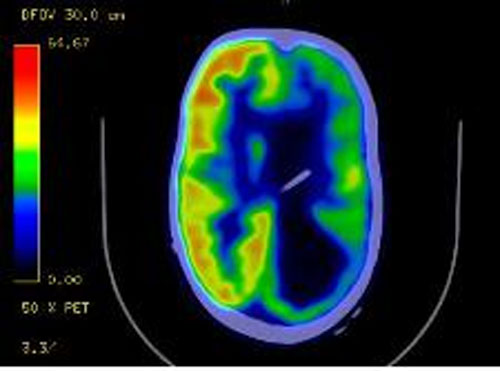

A scan of Olivia’s brain is pictured, and Amber Bush offers this explanation:

“The black on the pic is dead, useless brain. It does nothing, has no electrical activity….nada…just there taking up space. So, basically, Olivia has half of a brain. How amazing is that! She is such a miracle. The docs told us that if an adults brain looked like that, they would be a vegetable! Wow, isn’t God good! Her brain has reassigned all of that dead part to other parts of her brain. That is why they aren’t for sure what the part of her brain where the seizures are coming from controls. The more I look at it the more I see God in Olivia!”